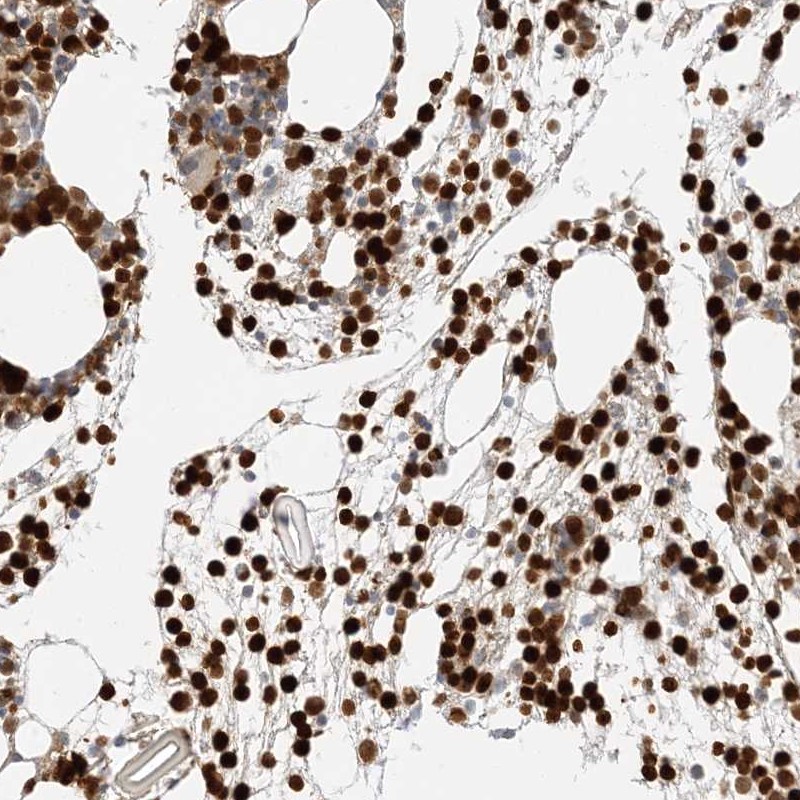

Immunohistochemistry analysis in human bone marrow and cerebral cortex tissues using Anti-GCA antibody. Corresponding GCA RNA-seq data are presented for the same tissues.